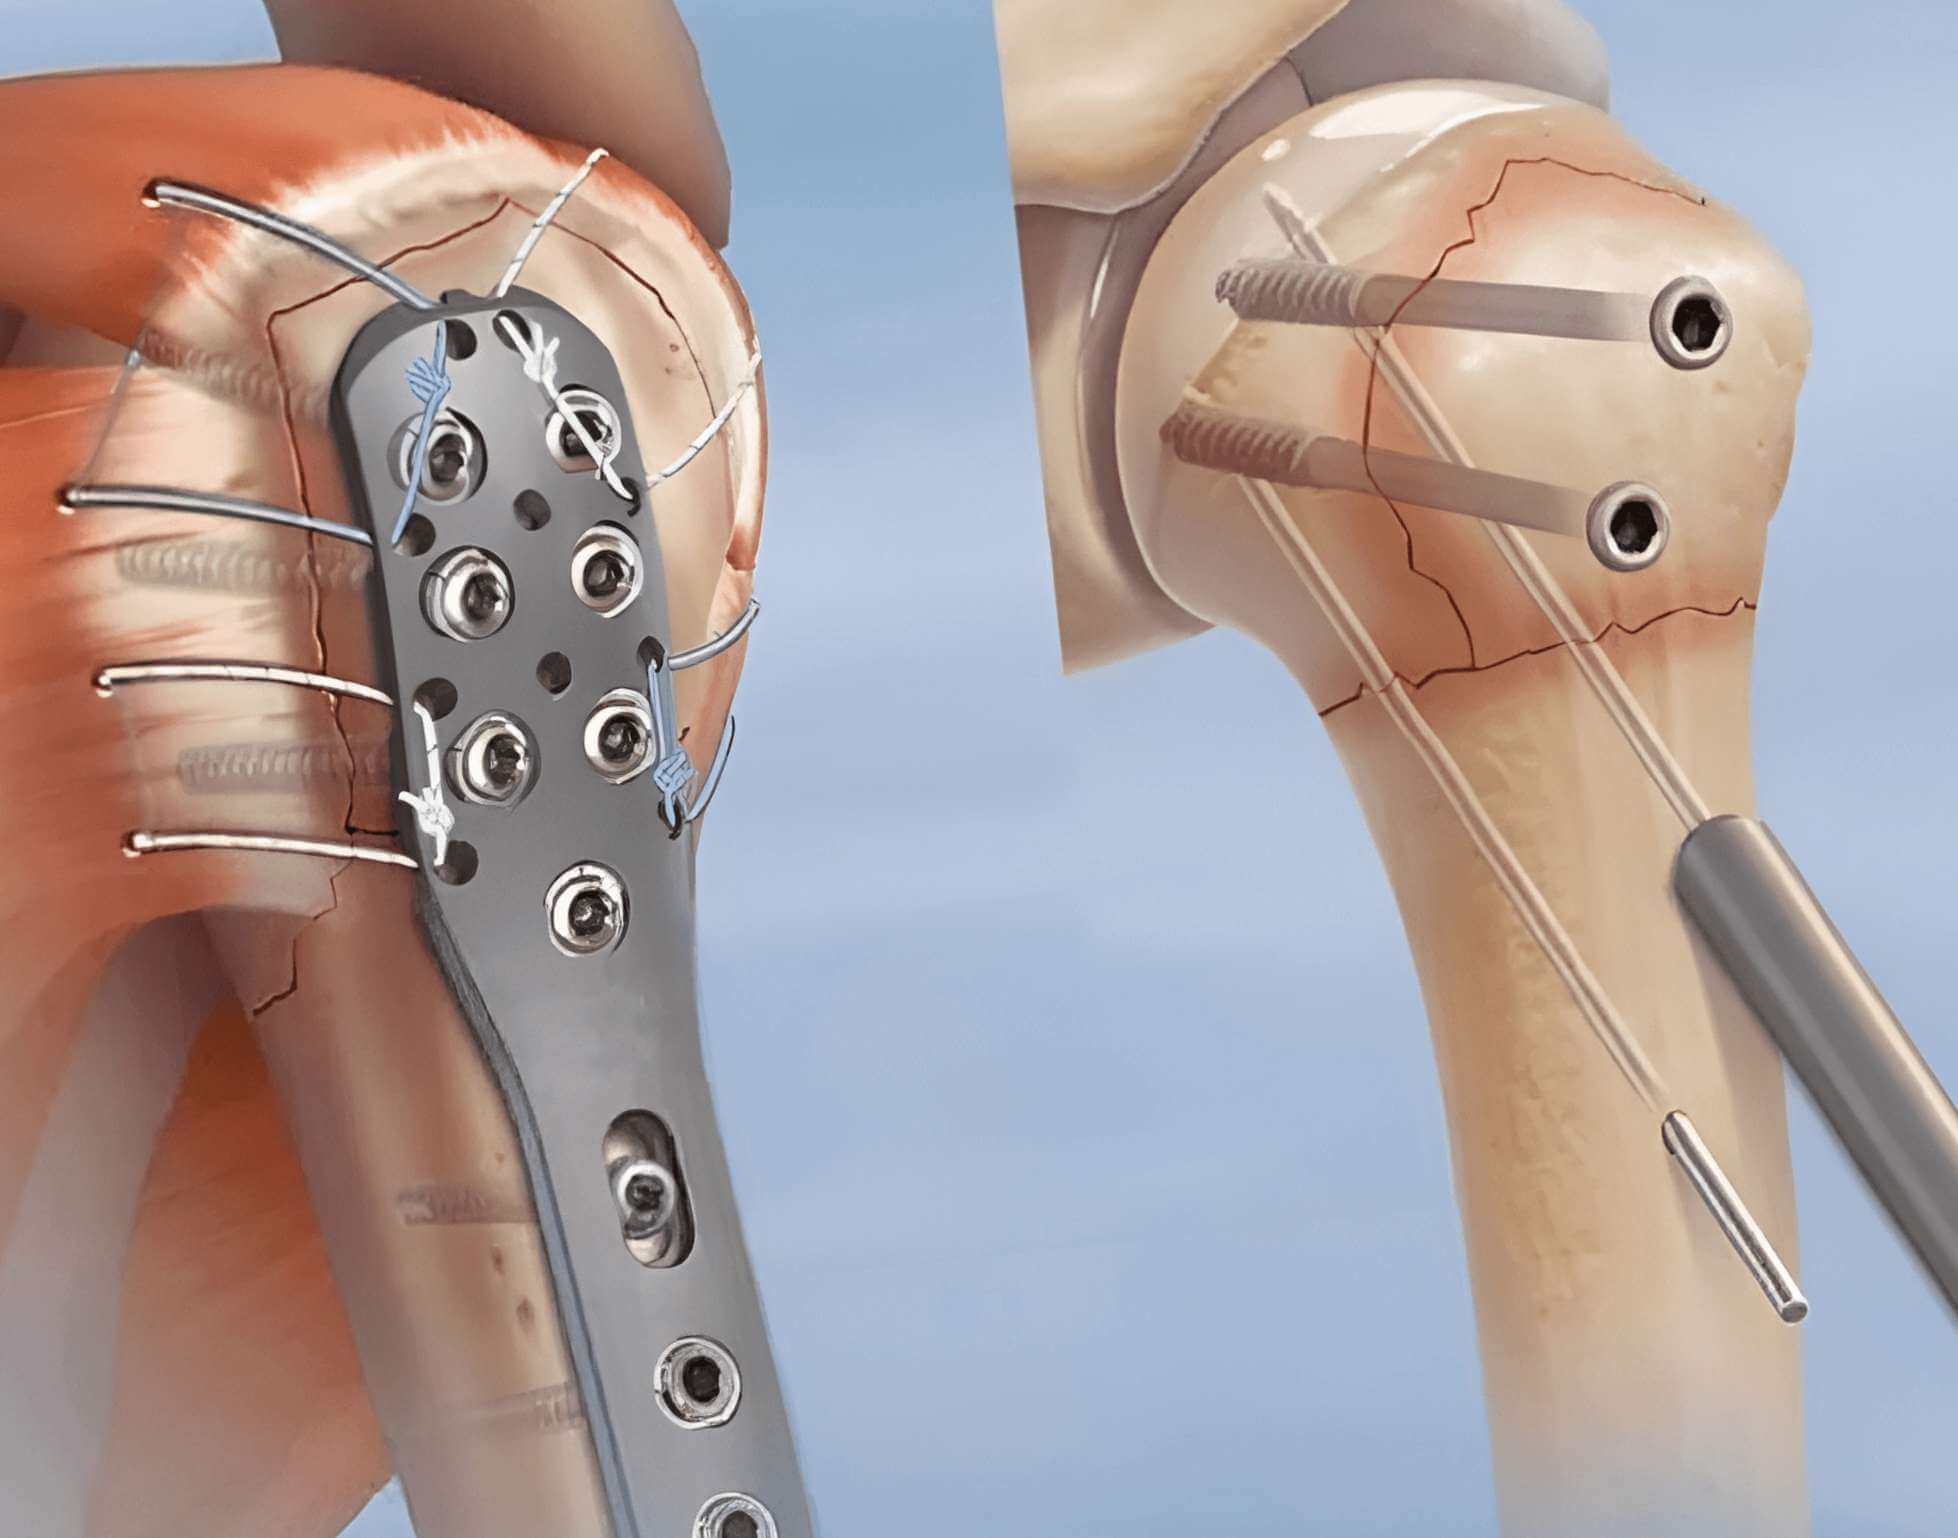

Остеосинтез коленного сустава

Остеосинтез коленного сустава 103 фотографий